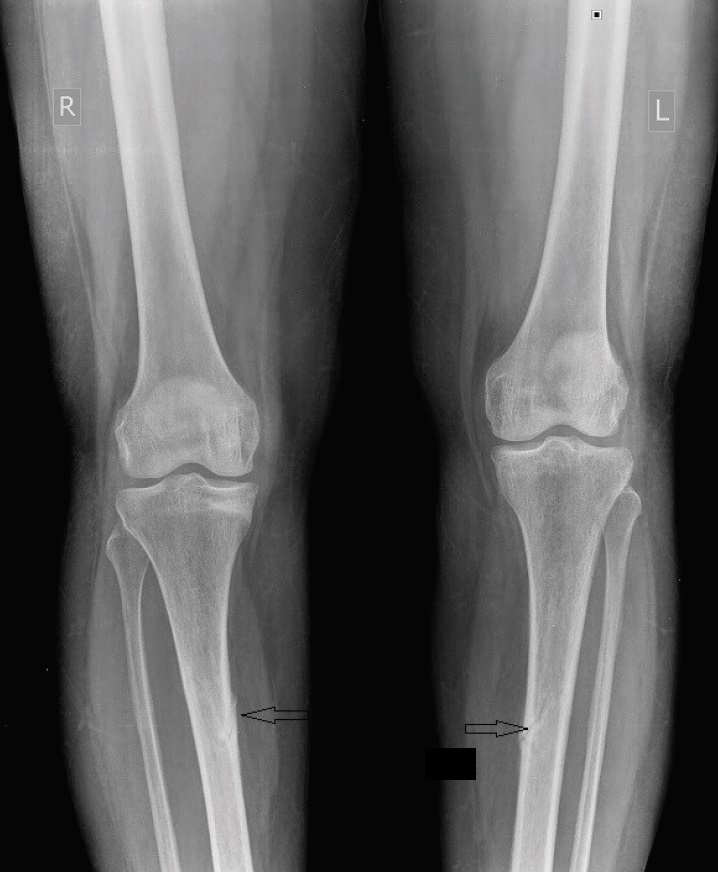

Radiological studies showed bilateral tibial shaft fractures, multiple fractures in bilateral tarsals (Figures 1 to 3). A PET Scan showed multiple insufficiency fractures of bilateral tibia, neck of right femur, metacarpal bones and scapula (Figures 4 to 7).

Figure 2.X-ray showing bilateral midshaft tibia fracture.